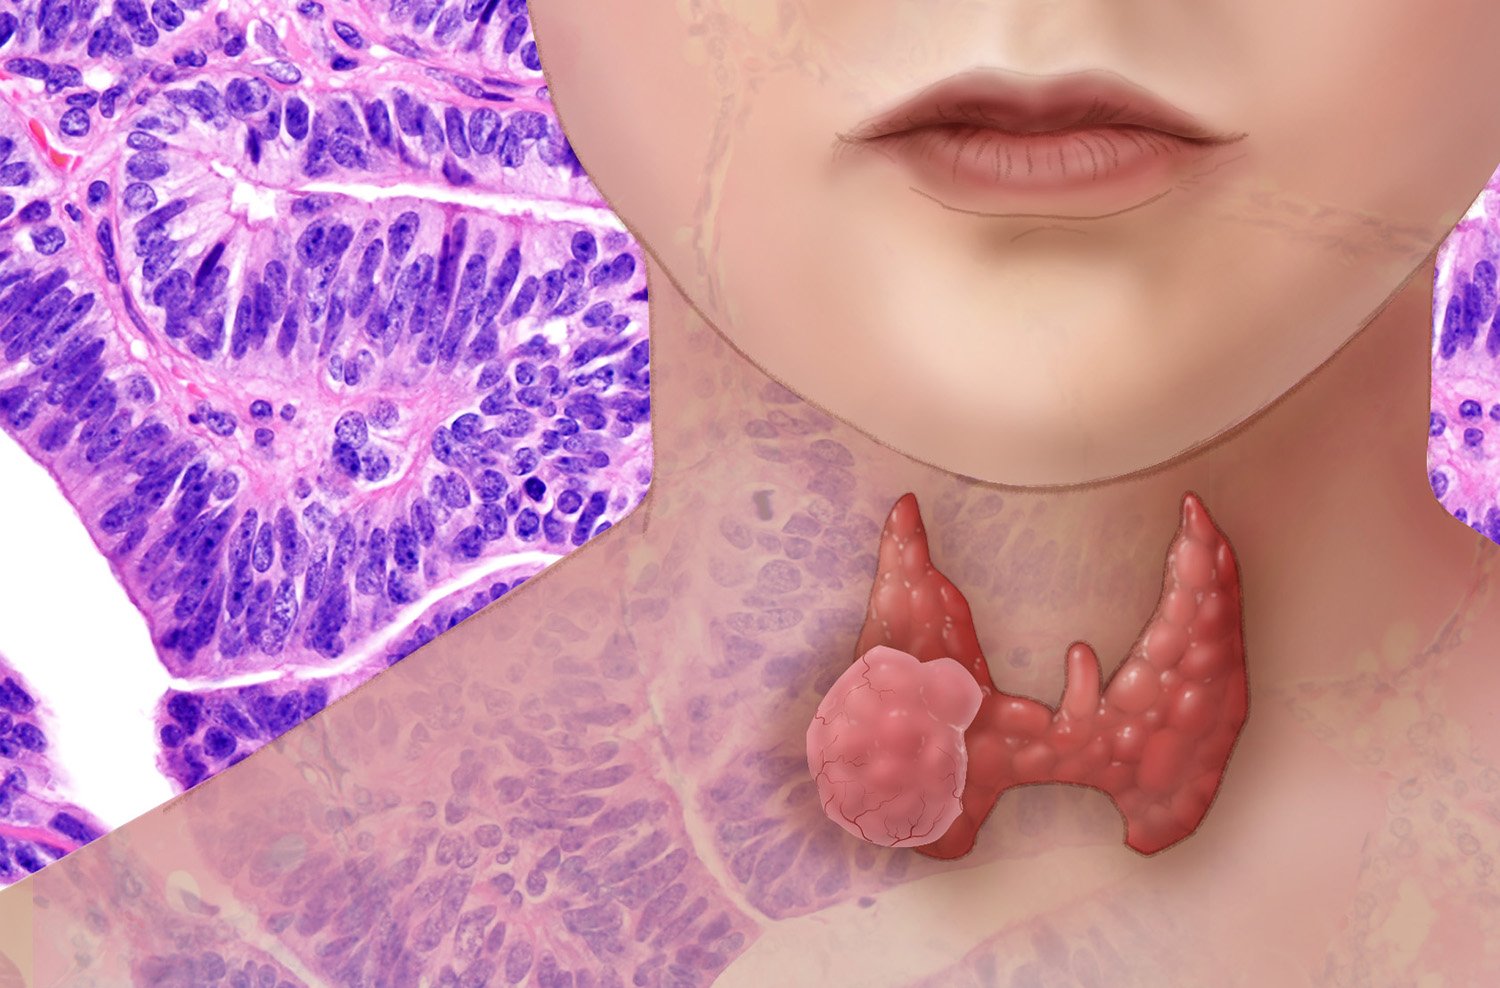

Фото раковой шишки на теле

Раковые шишки могут возникать не только на лице, но и на других частях тела. На фотографиях вы можете увидеть примеры раковых шишек на шее, руках, ногах и туловище. Обратите внимание на различные формы и размеры раковых шишек, а также на их внешний вид.